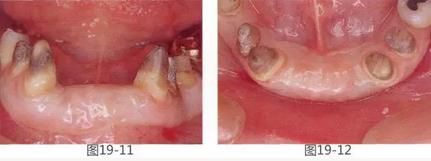

360截圖20170422142144525.jpg

圖19-1  將左下1,2,右下1,2拔除后4個(gè)月的正面照。

圖19-2  同時(shí)期咬合面照。佩戴臨時(shí)修復(fù)體后,由于易滯留食物殘?jiān)?,涂抹口紅困難而感到不滿。